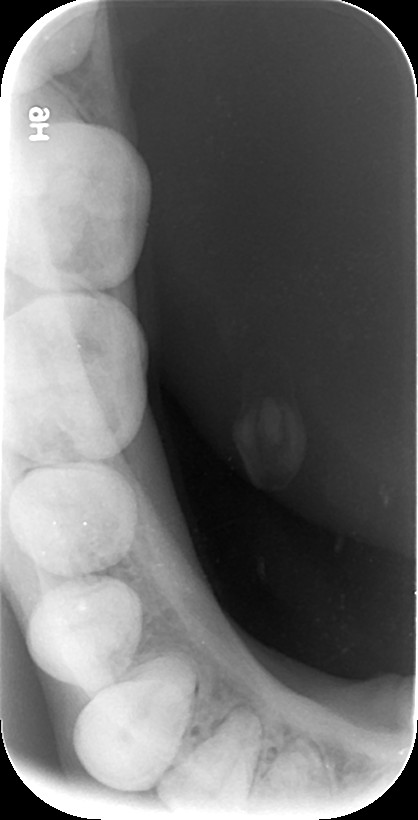

Με την οπισθομυλική ακτινογραφία επιτυγχάνεται η ταυτόχρονη απεικόνιση των μυλών των άνω και κάτω οπισθίων δοντιών ενός ημιμορίου (μιας πλευράς) με μία λήψη. Λαμβάνεται με την τοποθέτηση του ακτινογραφικού πλακιδίου εσωτερικά των δοντιών (προς την πλευρά της γλώσσας και του ουρανίσκου) και παράλληλα με αυτά. Χρησιμοποιείται ειδικός συγκρατητήρας οπισθομυλικών, τον οποίο δαγκώνει ο εξεταζόμενος.

Χρησιμοποιείται για την ανίχνευση τερηδόνων στις μύλες των δοντιών, κυρίως στις όμορες επιφάνειές τους (γειτνιάζουσες επιφάνειες δοντιών).

Η λήψη της είναι γρήγορη (διαρκεί λίγα δευτερόλεπτα) και ανώδυνη.